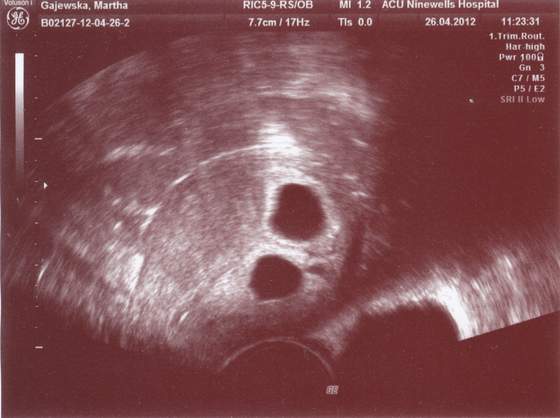

A na zdjęciu wspólnym widać tylko pęcherzyki

Zobacz załącznik 459766